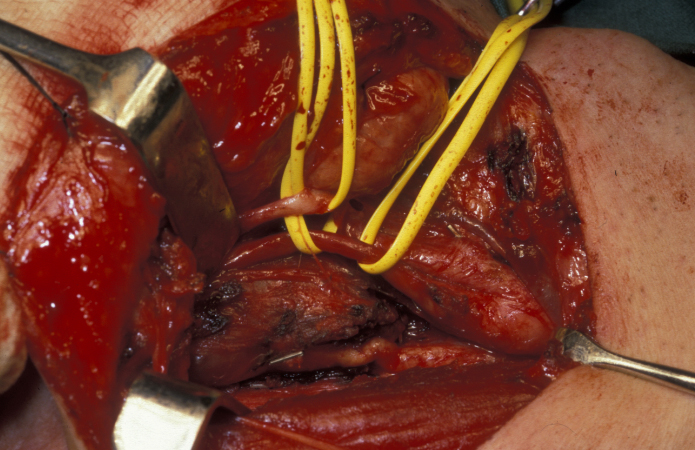

The majority of these neurogenic tumours (neurofibroma, Schwannoma) are slow-growing benign tumours. Approximately 25 to 40 % of these are found in the head and neck region. If possible / on balance, these tumours should be surgically removed: there is a small but significant risk of benign Schwannomas for malignant transformation (see Figure 3 and Figure 4).

Figure 4: Vagal schwannoma peeled out of the nerve sheath and preserving the structure of this important nerve. Note the resemblance to a new potato!